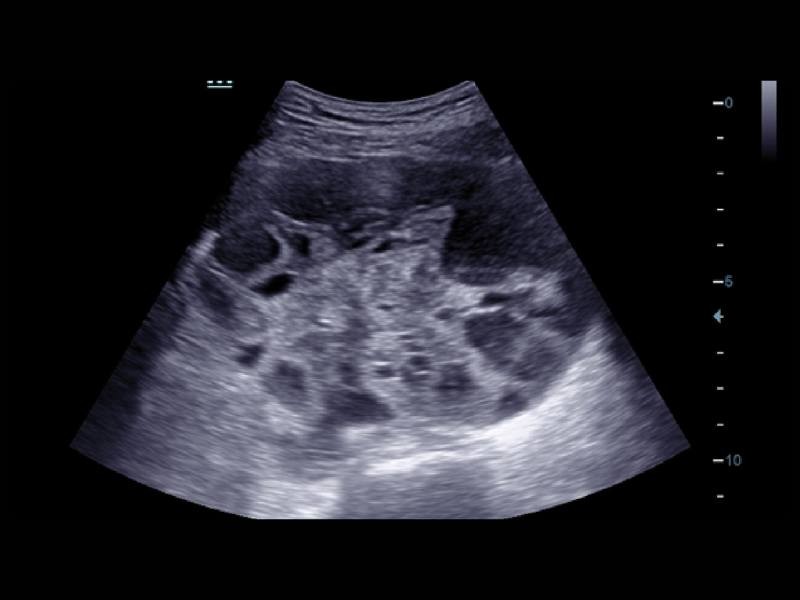

Em combinação com a exclusiva tecnologia 3T da Mindray (combinação de três camadas, design de corte total, controle térmico), os otimizados transdutores convexos, com feixe em fases e volume oferecem uma cobertura de aplicação mais extensa, resultando em uma excelente solução de varredura nas áreas de ABD, cardiologia, obstetrícia/ginecologia, entre outras.